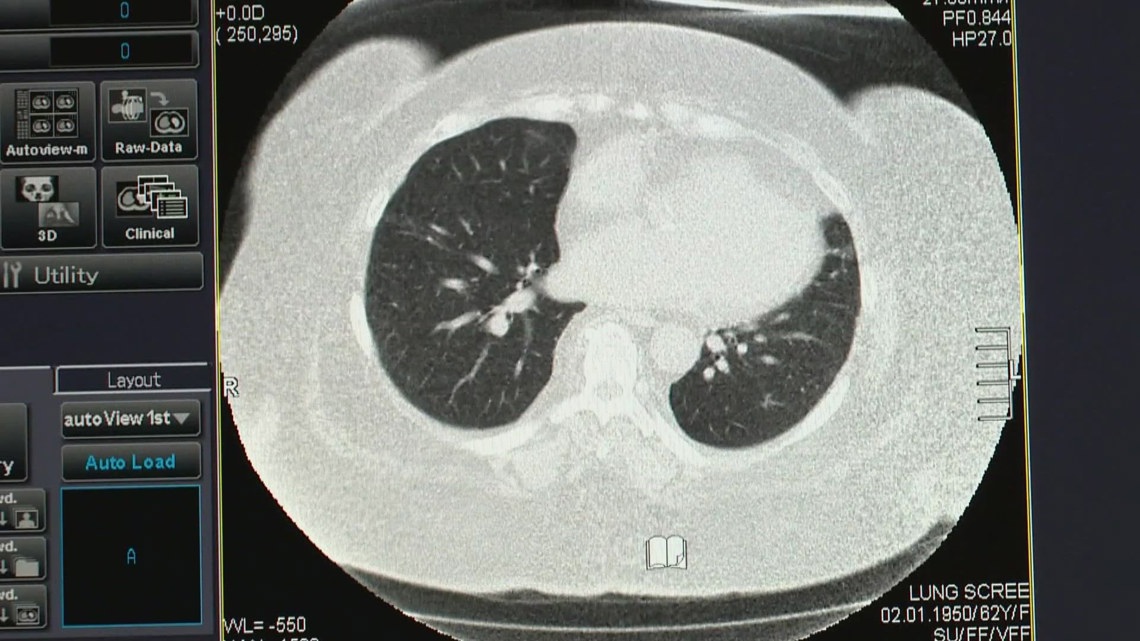

Un estudio de la Universidad de Virginia sugiere que las infecciones graves por COVID-19 o influenza podrían aumentar el riesgo de cáncer de pulmón, mientras que la vacunación podría ayudar a reducirlo.